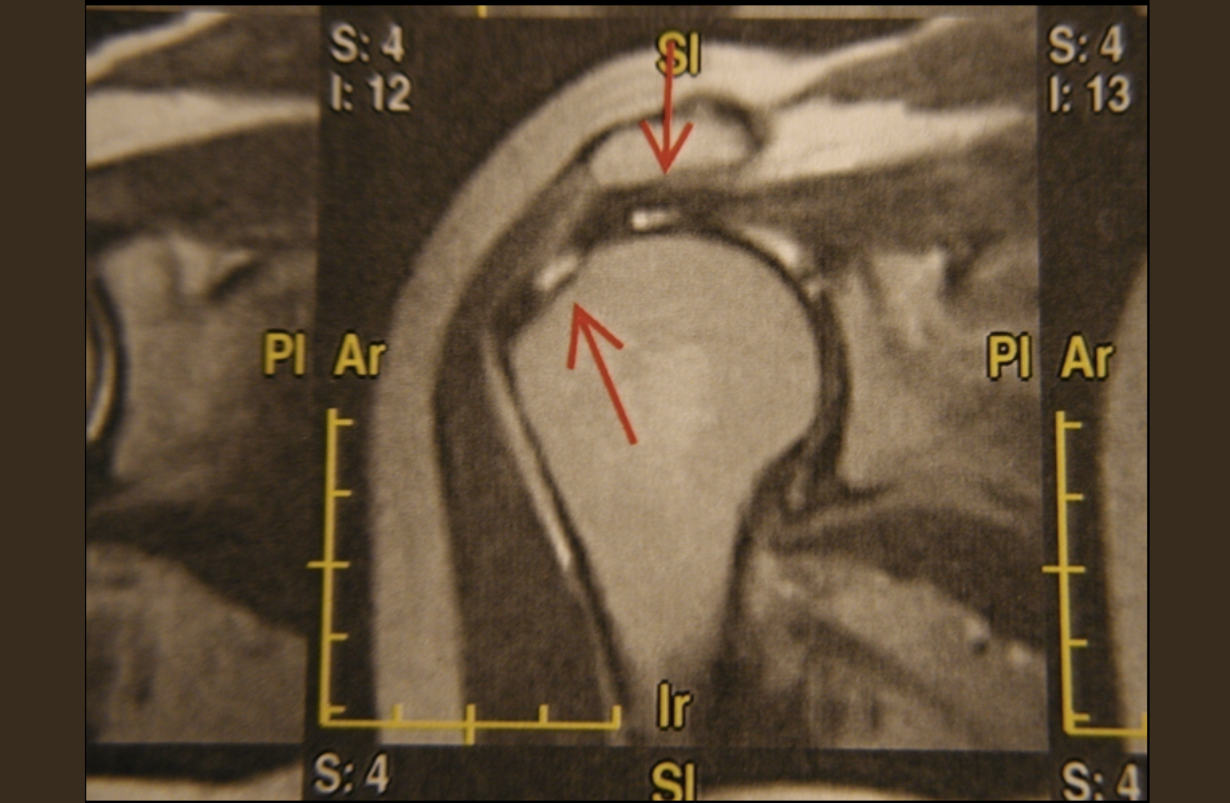

Labral Tear of Shoulder

The shoulder joint is surrounded by a capsule that contains the thick and well-balanced synovial fluid, which lubricates the joint and provides nourishment and oxygen to the cells that create and conserve the joint's collagen. The capsule may be torn through athletics , particularly overhead athletics, repetitive activities, and trauma, e.g., a fall on outstretched arm. Generally the tears are in the superior labrum, where the anchor of the long head of the biceps muscle enters the joint. these are called SLAP tears ((superior labrum anterior posterior). Rest with intermittent range of motion therapy is recommended. Please see the section on adhesive capsulitis, frozen shoulder. If healing does not occur in 6-8 weeks, consult a physician.